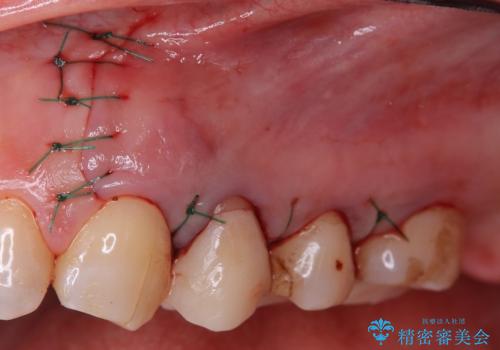

治療介入における意思決定が重要となるケースでしたが、患者と相談して①再根管治療→②外科的歯内療法という流れで治療を行いました。

結果、根管内にはイスムスにデブリが多く見られたものの破折線は確認できませんでした。再根管治療後、症状の経過を3ヶ月ほど確認しましたが打診、違和感が消失しておらず、外科的歯内療法を行うこととなりました。

違和感という主訴に対しては、非歯原生疼痛の可能性も考慮し、専門医院への対診を優先して行うことがありますが、今回は打診が陽性だったため、患者さまの希望もあり外科を行いました。

結果、症状改善し治癒良好と判断できます。

歯根端切除術後は1週間ほど痛むことがあります。